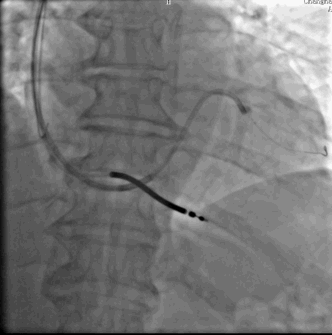

•造影情况:LAO发现走形左室侧的靶静脉与主干分支处有迂回夹角,且靶静脉中似乎也有夹角?

•选择SION软导丝0.014X180cm,头端塑形回头弯,无法进入靶血管

在美敦力的Attain Select TM+SureValveTM6248VI-130(鞘中鞘)引导下,Sion导丝顺利通过靶静脉第一个夹角,但是在继续推进导丝的时候却发现导丝打圈难以前进。

“猪尾圈”状靶血管导丝无法前进,容易弹出